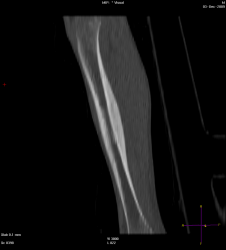

Мальчик 8 лет, был направлен травматологом к нам, с жалобами: на ноющую боль в голени в течении 2 мес., преимущественно усиливающася в ночное время, но проходящая после приёма НПВС. Провели МСКТ:

Думаю, что большого труда не составит определиться, что это за патологическое состояние, хоть и был отход от "классики". Случай ещё пока не верифицирован!

Остеоид-остеома. А в чем отход от классики?

Диф.ДЗ с первично-хроническим остеомиелитом.

Интересное наблюдение, но для "классики" остеоид - остеомы не хватает - пуговки - подобия секвестра в полости, но это в любом случае хронический остеомиелит подлежащий оперативному лечению.